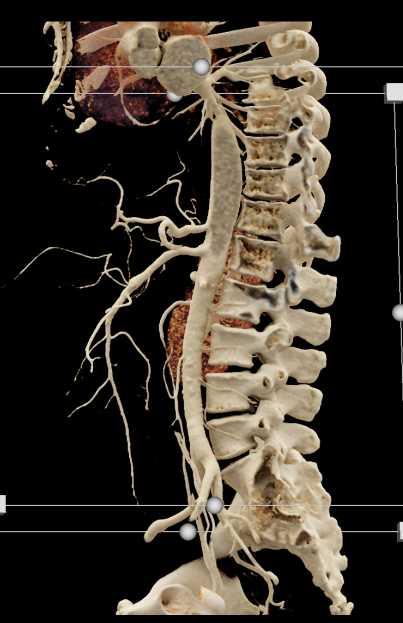

Diagnosis

SMA Stenosis